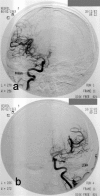

Moyamoya disease is a progressive vasculopathy leading to stenosis of the main intracranial arteries. The incidence of moyamoya disease is high in Asian countries; in Europe and North America, the prevalence of the disease is considerably lower. Clinically, the disease may be of ischaemic, haemorrhagic and epileptic type. Cognitive dysfunction and behavioral disturbance are atypical symptoms of moyamoya disease.Characteristic angiographic features of the disease include stenosis or occlusion of the arteries of the circle of Willis, as well as the development of collateral vasculature. Currently, magnetic resonance angiography and CT angiography with multi-row systems are the main imaging methods of diagnostics of the entire range of vascular changes in moyamoya disease.The most common surgical treatment combines the direct arterial anastomosis between the superficial temporal artery and middle cerebral, and the indirect synangiosis involving placement of vascularised tissue in the brain cortex, in order to promote neoangiogenesis. Due to progressive changes, correct and early diagnosis is of basic significance in selecting patients for surgery, which is the only effective treatment of the disease. An appropriate qualification to surgery should be based on a comprehensive angiographic and imaging evaluation of brain structures.Despite the rare occurrence of moyamoya disease in European population, it should be considered as one of causes of ischaemic or haemorrhagic strokes, especially in young patients.